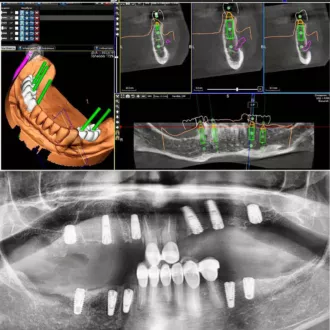

- выполнение рентгенограммы и КТ запланированного места имплантации для определения плотности челюстной кости, степени ее атрофии, наличия возможных патологических очагов

- планирование этапов имплантации и моделирование внешнего вида будущего зубного ряда